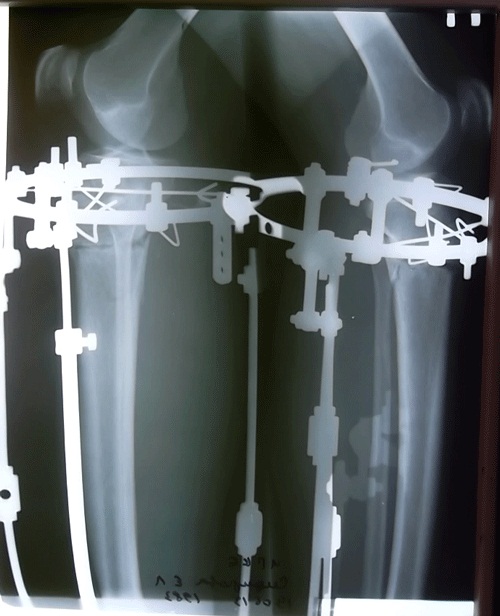

Рентгеновские снимки перед снятием аппаратов.

Вложения

SAM_6374.JPG

SAM_6373.JPG